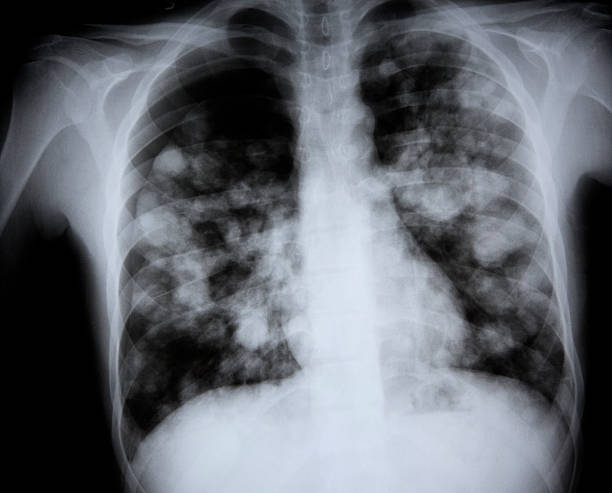

급성 폐렴의 정의

급성 폐렴은 폐의 염증으로 인해 발생하는 질병으로, 주로 세균, 바이러스, 곰팡이 등의 감염에 의해 유발됩니다. 이 질병은 폐의 공기 주머니인 폐포에 염증이 생겨 가스 교환이 원활하지 않게 됩니다. 급성 폐렴은 특히 면역력이 약한 노인이나 어린이에게 치명적일 수 있습니다.